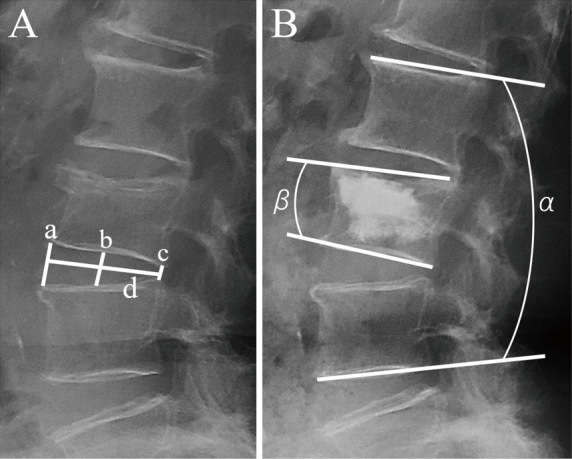

Adjacent vertebral fractures after balloon kyphoplasty are speculated to occur in association with increased mechanical pressure due to rigid cement-augmented vertebrae. This study aimed to clarify whether adjacent vertebral fractures are more likely to occur after balloon kyphoplasty for osteoporotic vertebral fractures when the intervening adjacent disc degeneration is advanced. We retrospectively reviewed the findings for 99 patients who underwent balloon kyphoplasty for the first-ever osteoporotic vertebral fracture at the thoracolumbar junction levels (T11-L2). Radiological parameters and clinical data were compared for the cranial and caudal vertebrae between the groups with and without adjacent vertebral fractures within 1 year postoperatively. Postoperative adjacent vertebral fractures occurred in 20 patients (12 cranial adjacent vertebral fractures and eight caudal adjacent vertebral fractures). The cranial mean disc height was 5.87 ± 1.48 mm in the cranial adjacent vertebral fracture group and 7.98 ± 1.73 mm in the non-cranial adjacent vertebral fracture group (p < 0.01), and the caudal mean disc height was 6.24 ± 1.83 mm in the caudal adjacent vertebral fracture group and 9.55 ± 2.03 mm in the non-caudal adjacent vertebral fracture group (p < 0.01). According to receiver operating characteristic analysis, the optimized cutoff values of cranial mean disc height for cranial adjacent vertebral fracture occurrence and caudal mean disc height for caudal adjacent vertebral fracture occurrence were 6.37 mm and 7.70 mm, respectively. Multiple logistic regression models showed increased odds ratios for low disc height and large cement volume for cranial adjacent vertebral fractures and low disc height and cement leakage for caudal adjacent vertebral fractures. In conclusion, patients with advanced preoperative degeneration of the adjacent disc showed a higher incidence of adjacent vertebral fracture after balloon kyphoplasty.